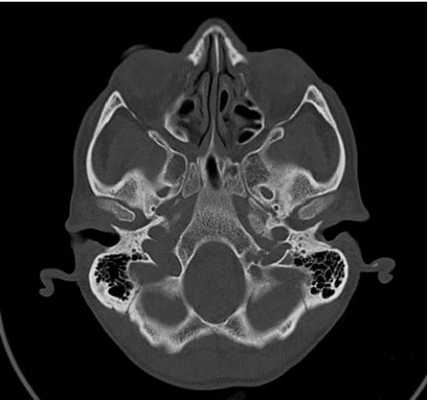

КТ основания черепа

КТ основания черепа - метод медицинской визуализации, основанный на использовании рентгеновских лучей, и применяющийся для диагностики патологических процессов, локализующихся в нижних отделах черепной коробки. Позволяет получать серии послойных снимков области интереса, толщиной от 0,5 мм, с высоким разрешением и четкостью. Благодаря этому компьютерная томография - один из самых точных и достоверных методов диагностики, незаменимый при некоторых патологиях и заболеваниях мозговой части черепа.

Снимок КТ основания черепа

Что покажет КТ основания черепа

На снимках, полученных во время обследования, визуализируются анатомические и костные структуры основания черепа, включающие в себя основание мозга, ствол мозга, черепно-мозговые нервы, краниовертебральную область, область таламуса, гипоталамуса, гипофиза, турецкого седла, перекреста зрительных нервов. Исследуется нормальное строение вышеперечисленных анатомических образований, обнаруживаются участки с отклонениями от нормы в виде новообразований, кист, воспалительных процессов. Оценивается протяженность обнаруженных патологий, их связь с окружающими органами и тканями. Изучается влияние патологического процесса на функции ЦНС.

КТ основания черепа при переломах

Перелом основания черепа - последствие избыточных нагрузок на тело человека, соответствующих травмам при падении с высоты, дорожно-транспортных происшествиях, авариях, ударном воздействии. Состояние пациентов в таких случаях оценивается как тяжелое и крайне тяжелое. По этой причине КТ основания черепа у таких больных требует экстренной госпитализации в специализированное лечебное учреждение, оснащенное всем необходимым оборудованием. Обследование проводится с участием узких специалистов, таких как нейрохирурги, хирурги, реаниматологи, травматологи, невропатологи. По этой причине наш медицинский центр напоминает - при подозрении на переломы основания черепа необходимо срочно обратится за специализированной медицинской помощью, а не заниматься самодиагностикой.